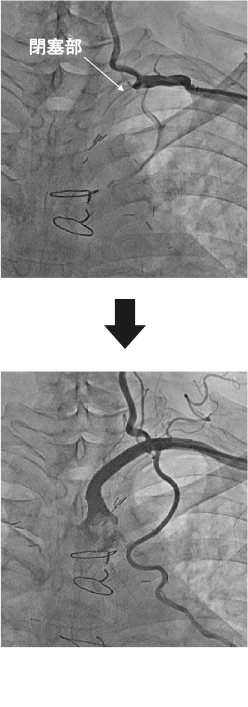

肘や足の付け根から局所麻酔をして、管を入れます。細い管(カテーテル)を血管の中に通し、ガイドワイヤーという細い針金で狭くなった(あるいは詰まった)血管を通し、バルーン(風船)をふくらませて血管を広げます。血管が広がったら、ステントと呼ばれる金属製の網状の管を入れて固定し、再び血管が詰まるのを防ぎます。ただし治療の場所によってはステントが留置できないこともあります。

所要時間は約1~2時間程度で、傷口は小さくてすみます。入院期間は2-4日程度です。患者さんの負担が少ない低侵襲な治療ですので、現在、内科的治療の主流になっています。腎臓の機能が悪い患者さんには造影剤を使用せずに炭酸ガスで治療することが可能です。造影剤を使用しないことで腎臓への負担を軽くできます。